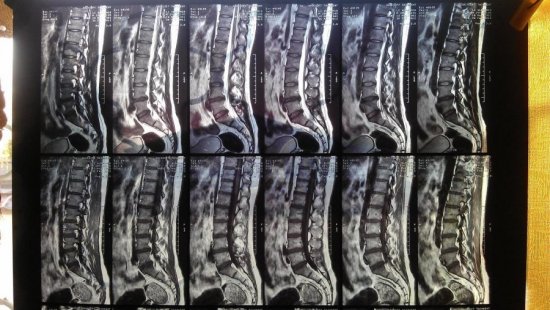

Обращаются к доктору для последующей диагностики и лечебных мер. Важно помнить, перед тем, как проводить мануальные способы лечения на позвоночнике, мануальный терапевт обязан направить больного на компьютерную или магнитно-резонансную томографию. Если диагностирована межпозвоночная грыжа большого размера, то показана операция. Грыжа удаляется, нервные корешки восстановятся, боль пройдет.